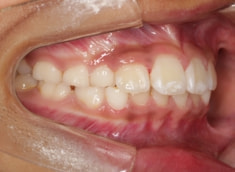

症例紹介

小児期ケース:叢生(ガタガタ)

治療法:拡大プレート+フルパッシブブラケット(クリアスナップ)

治療前